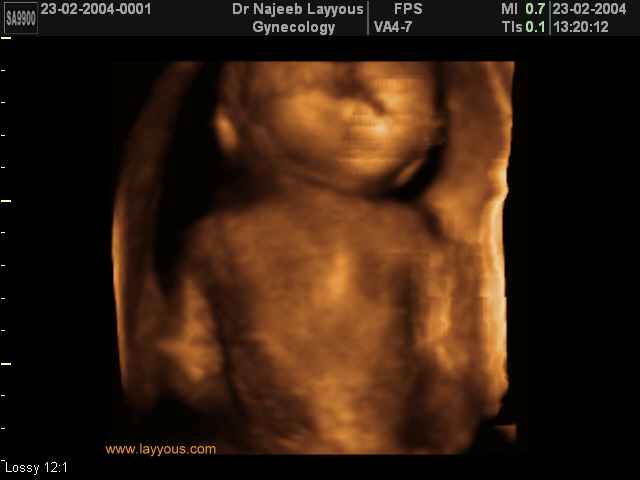

صور لأعضاء الجنين بجهاز الموجات فوق صوتية ثلاثي الأبعاد | الدكتور نجيب ليوس

صور لأعضاء الجنين بجهاز الموجات فوق صوتية ثلاثي الأبعاد